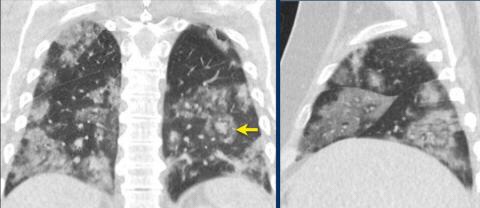

CORADS 5

Case 1

Multifocal GGO and consolidation

Case 2

10 days of complaints.

CT: bilateral multifocal GGO, vascular thickening (circle), subpleural bands (arrow).

PCR: positive

Case 3

Eleven days of complaints

CT findings: Bilateral GGO and consilidation, basal preference, vascular thickening (circle).

CORADS 6

Patient with positive PCR and bilateral GGO.

Notice halo sign (arrow).